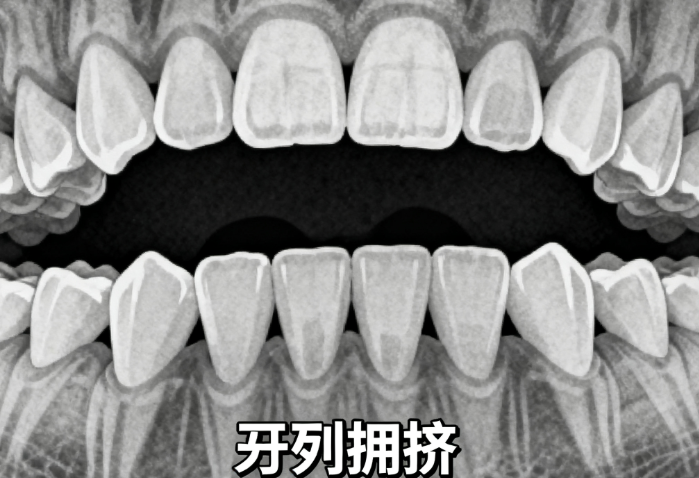

矫正难度越高,价格也会相应提高。对于简单病例,如轻度拥挤,费用可能降低30%至50%。而对于复杂病例,如较重的龅牙或地包天,费用可能高达7万元至8万元。